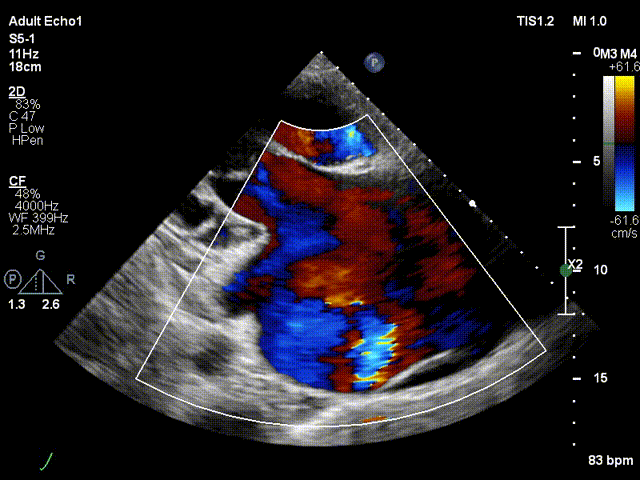

术前超声

巨量三尖瓣反流 [平均缩流颈宽度2.37 EROA 2.01 返流量140ml]